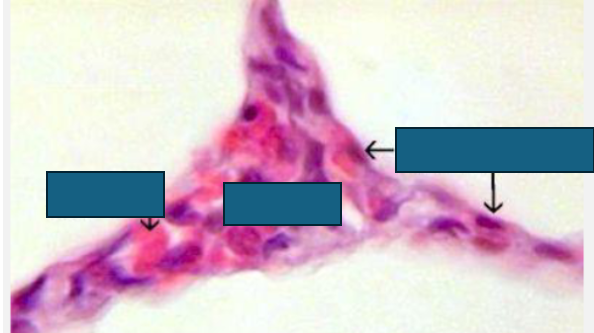

alveolar fibrosis

thickening of alveolar wall

higher diffusion distance→ less O2 in lungs